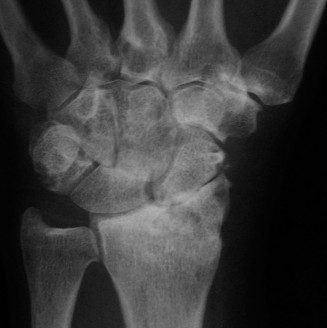

Use 1-2ICSRA to revascularize the scaphoid? CASE 3 ### A patient is brought into the emergency room following a motor vehicle accident. He complains of severe pain in his wrist. Physical examination reveals a tender and swollen wrist. X-rays (Figs. 3–5A–B) are as follows. What is your diagnosis?

Figure 3–5 A–B. (©) Sunil Thirkannad and Christine M. Kleinert.

The correct answer is (D). This x-ray reveals a perilunate injury of the wrist. It is important to be aware of the various radiological parameters that reveal disruption of carpal alignment. Literature suggests that a perilunate injury is missed as much as 25% to 40% of the times. Which radiological signs of perilunate injury can be seen on the above Figs. 3–5A–B .

The correct answer is (E). All three radiological signs are seen on this x-ray. Triangle sign refers to the shape of the lunate seen on the PA view. A normal, well located lunate looks like a tilted trapezium. A triangular-shaped lunate suggests that it is in a hyperflexed position. In the lateral view, a subluxated and volar-tilted lunate has the appearance of a “spilt teacup.” In the above x-ray, Gilula’s first and second lines are broken.